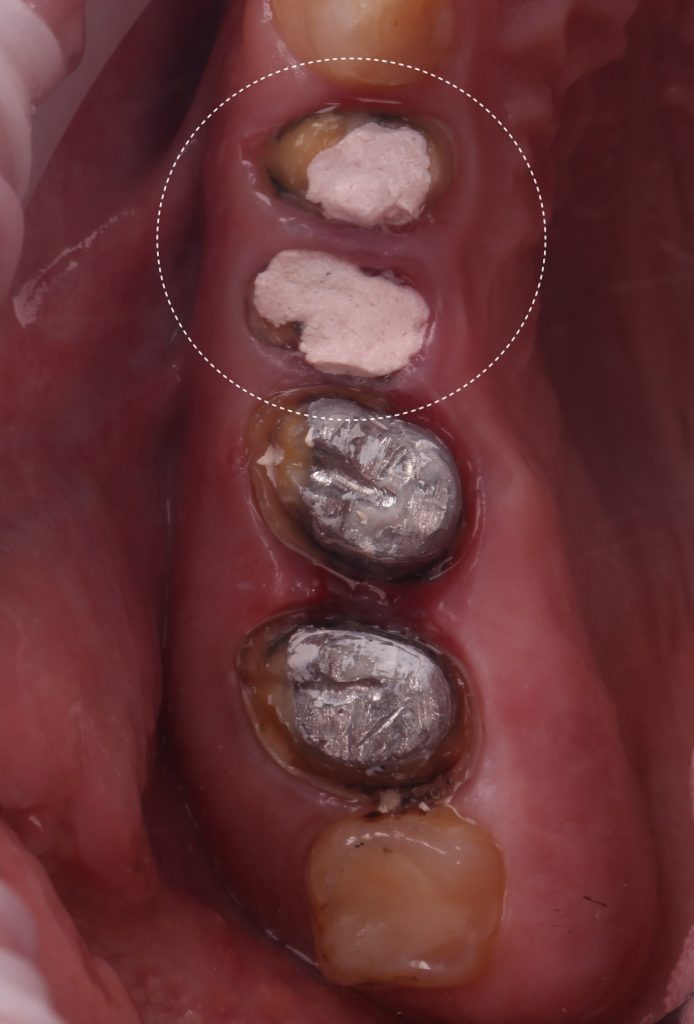

Die endodontische Behandlung wurde durchgeführt.

Fallstudie - Kieferorthopädischer Behandlungsplan nach Zahnextraktion 9

Es wurde genügend Hartgewebe über der Gingiva gewonnen, um einen Ferrule-Effekt zu erzielen. Die erste Phase der prothetischen Rehabilitation wurde mit dem Einsetzen der provisorischen Kronen abgeschlossen.